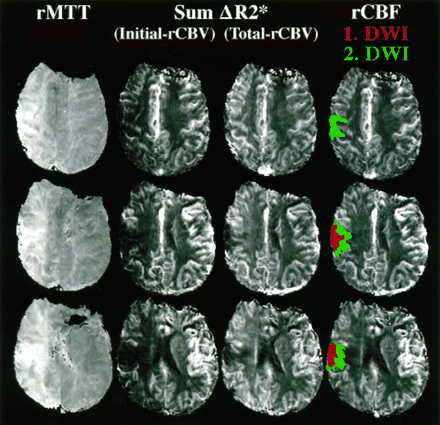

图2。这个图展示了水平切片两种不同脑血容量cb v()都未地图(cb v初始相对[rCBV],都未总rCBV),相对平均运输时间(rMTT)地图,和一个图像代表相对脑血流量(rCBF)。看到更多的细节关于这些图片的方法计算。

基于先前建立缺血半影和出版的特点,1,5,11我们开发了一个操作性定义的组织梗塞的风险使用回顾性方法的进展。第一个发现的病变扩散研究表明在我们的操作模型缺血性核心(图3和图4⇓)。初始扩散之间的不匹配区域病变及其扩展了后续醉酒驾车研究后的24到72小时第一个定义操作半影。从第一天使用灌注研究,指标CBV(初始rCBV、峰值rCBV总rCBV)和流(rCBF) rMTT,以及ADC值测定在三个地区(见定义图3和图4⇓):1)酒后病变时间点1(代表我们的操作缺血性核心),2)之间的不匹配区域首次和后续醉酒驾车研究(代表我们的操作半影),和3)侧半球,影响严重的地区反映第一醉酒驾车病变程度和解剖位置。镜子地区必须在10%的醉酒驾车病变的大小必须在同一时间点1,对侧半球的解剖定位。排除可能从intrasulcal工件或蛛网膜下腔CSF,我们手动放置这些地区所有片上,他们可以被识别,并计算意味着跨片(加权体素)的数量为每个定义的操作区域。

均值(±标准平均误差(SEM))放大扩散异常在整个集团的376.6%(±206.5)比较第一次醉酒驾车和随后的酒后驾车,这是平均48(±6)小时后。醉酒驾车发生异常的扩大在该地区的低灌注的患者。所有患者的异常灌注区域大于驾车在初始扫描时间点异常。的平均体积异常灌注(使用MTT异常灌注异常的标志)是96.6毫升(±16.9)和醉酒驾车的异常是28.6毫升(±8.3)在初始时间点和59.2毫升(±15.4)在第二个时间点。二十二岁的25例有慢性t2加权扫描完成平均量66.6毫升(±15.9)。异常的平均增加慢性T2体积与最初的醉酒驾车相比体积在整个组患者467.0% (±182.4)。图4演示了一个代表病人的研究人群与皮质醉酒驾车病变和更大的一个小灌注异常,包括一个主要部分的大脑中动脉的领土。的扩散增大66%(比较第一天和第二天)发生在oligemic领土。减去醉酒驾车更扩大病变的病变在第一天的后续研究代表了缺血半影操作模型。

之间的各种估计rCBV,最初的操作半影rCBV是最好的预测。最初rCBV反映曲线下的面积曲线的初始部分,因此指数加权的rCBV流入血液的体积。最初rCBV非常类似于rCBF在这项研究中,这中可以看到图2而在表1显示类似的比例差异半影和缺血性核心定义的操作。虽然最初的rCBV显著降低,总rCBV显著增加的运营半影侧控制区域。然而,总rCBV不如最初rCBV差异化运营从缺血半影的核心。rCBV总数的增加在我们的操作半影同意大多数宠物cb v测量显示增加缺血半影中都未引起的早期代偿反应脑灌注压降低。12,13rCBF略优于初始rCBV在区分半影从核心定义的操作。rMTT显著延长操作半影,更在缺血性核心。然而,rMTT是不如其他标记区分从缺血半影核心定义的操作,但在区分异常(即是一个优秀的标志。,核心和半影)从正常灌注(见表1)。